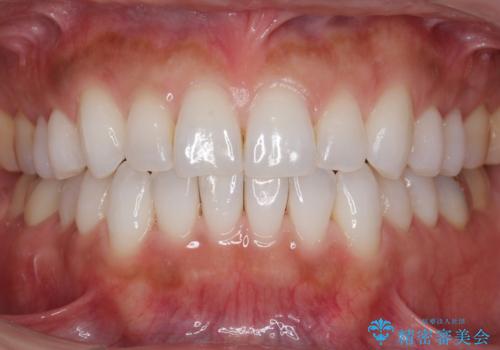

30代女性 前歯のがたつき

- 30代女性

- 前歯のがたつきを主訴に来院。

右下の奥の銀歯も治療しています。

下の前歯を下げるため、IPR(歯をわずかに削る処置)を行っています。